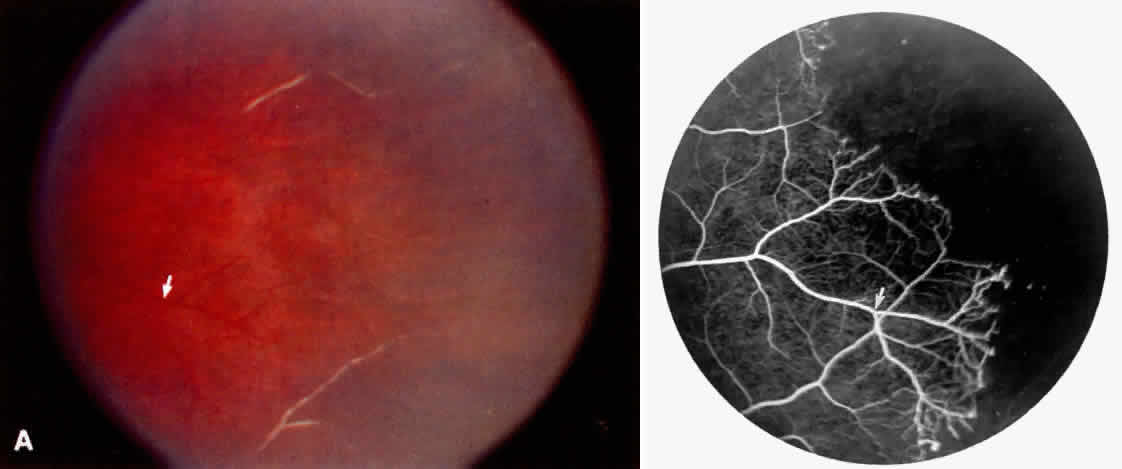

Disc Sign

Transient dark red spots (similar to conjunctival commas), representing plugs of sickled erythrocytes within superficial capillaries, may be seen on the surface of the optic disc (Fig. 3 and Color Plate 1A). These disc changes are not associated with any functional or anatomic abnormalities. They are found in 11% of all patients with sickle cell disease, but appear to be more common in patients with homozygous sickle cell anemia, occurring in 29% of these patients.67 The disc sign correlates with the presence of conjunctival commas and ISCs.